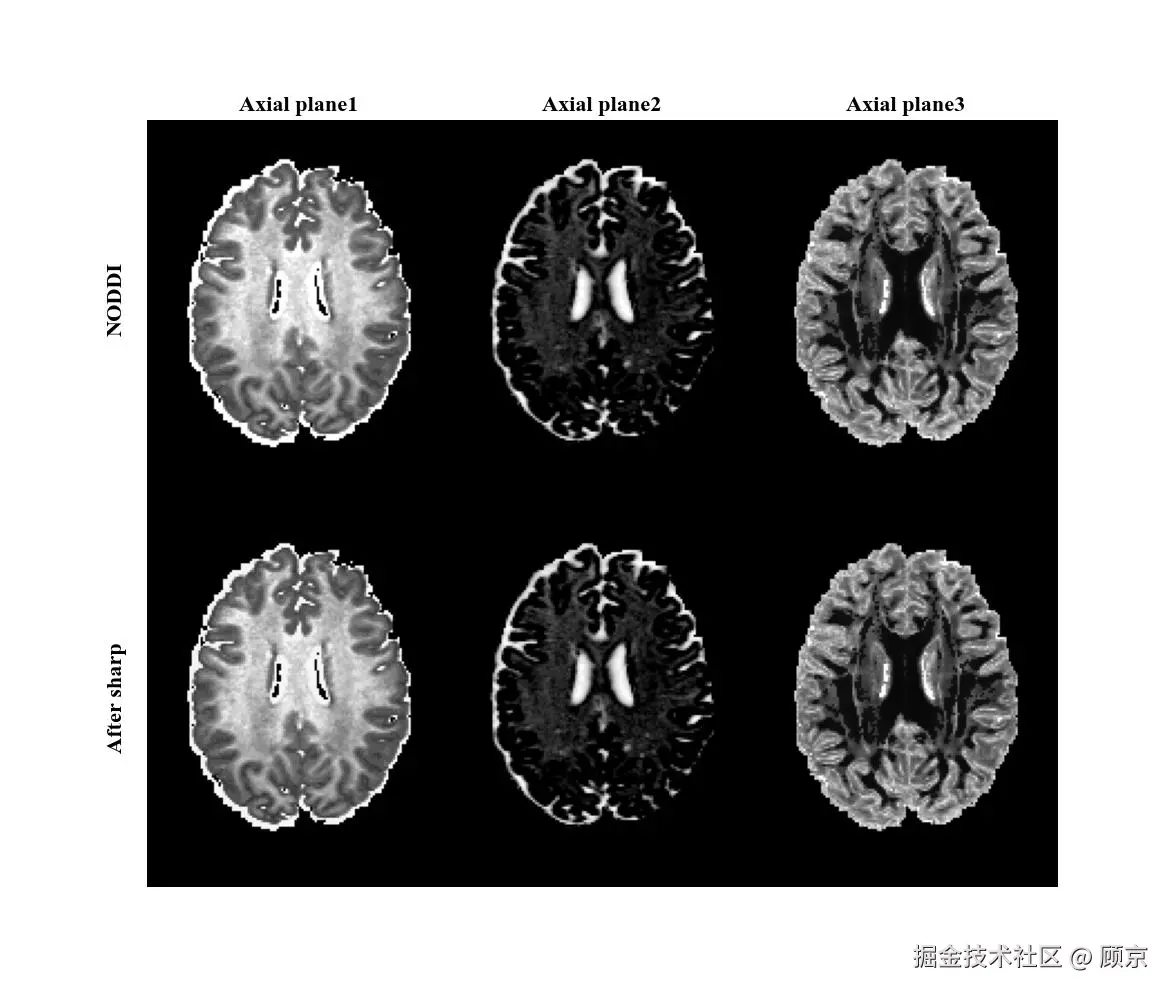

图像锐化可以补偿图像的轮廓,增强图像的边缘及灰度跳变的部分,使图像变得清晰。这不是降级操作,是增强操作,不过也一起整理在这儿吧,如图4所示。

图4 锐化操作